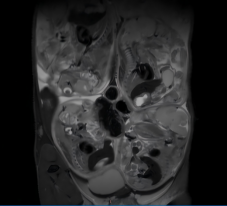

常规T2序列扫描(怀孕小鼠)

清晰显示胎盘结构、胚胎轮廓及羊水分布